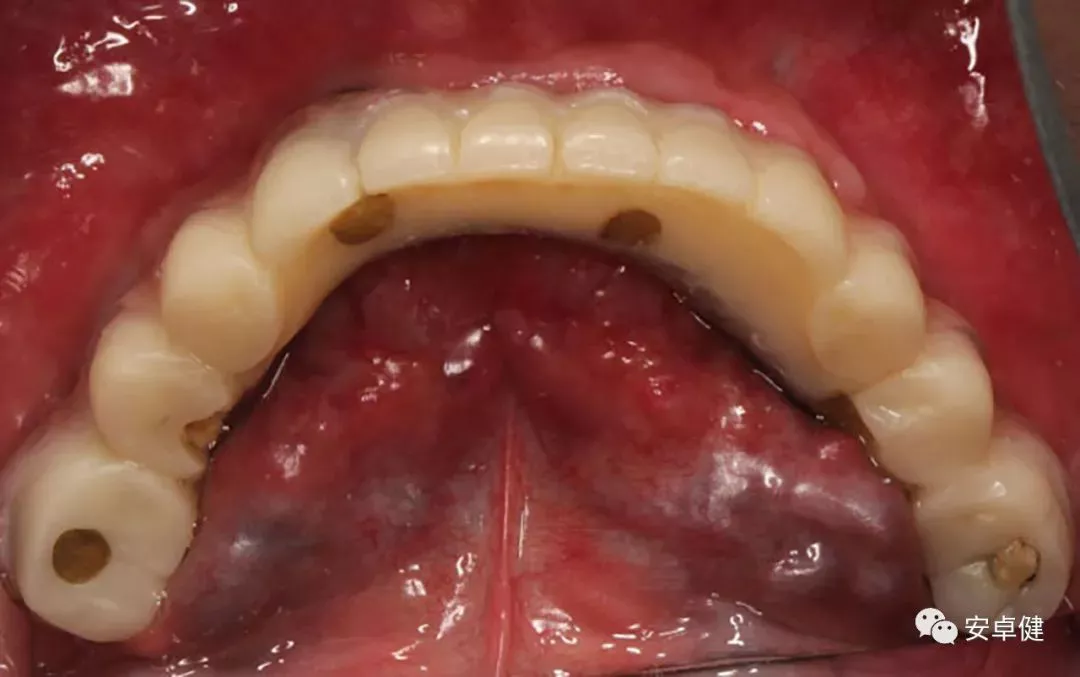

▷ 口内检查

• 上颌可见11、12、13、14、15、21、22、23、24行烤瓷桥修复;

• 16、17、25、26、27行栓道附着体可摘局部义齿修复;

• 下颌可见31、33、41、42、43、44烤瓷桥修复;

• 34、35、36、37、45、46、47行栓道附着体可摘局部义齿修复;

• 口腔卫生状况不佳,全口牙龈红肿;

• 下颌前牙烤瓷桥松动,修复体边缘不密合;

• 牙槽嵴低平,前庭沟深度较浅。

种植术前下颌合面照